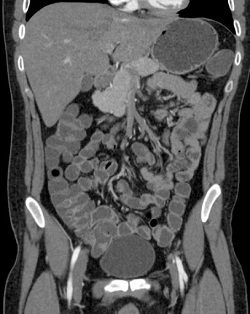

КТ кишечника с контрастом

Для диагностики патологий, поражающих кишечную стенку, на сегодняшний день нет более информативного и качественного метода исследования, чем КТ кишечника с контрастом. Введение специальных растворов на основе йода или бария позволяет существенно увеличить четкость получаемых изображений. С помощью компьютерной обработки данных достигается объемная визуализация элементов пищеварительного тракта со всеми нарушениями структуры тканей. Контрастный метод наиболее эффективен для обнаружения новообразований, патологий кровоснабжения кишечника, воспаленных и эрозированных участков.